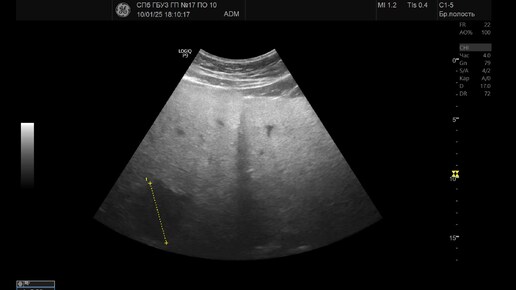

Ультразвуковая диагностика (УЗИ). Доктор Иогансен. Видеопримеры. Выпуск 111. Опухоль печени (5).